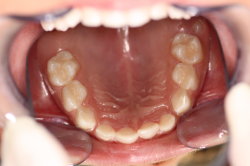

Leistungsspektrum - Kofferdam Zähne

Schön geschützt...

Fissurenversiegelung:

Die Backenzähne haben meistens tiefe Furchen und Rillen (Fissuren), die für die Reinigung mit der Zahnbürste oft schwer zugänglich sind. Speisereste und Bakterien können sich in diesen Fissuren festsetzen und Karies verursachen. Zum Schutz vor Karies empfiehlt es sich daher, die Rillen mit einem dünnfließenden, lichthärtenden Kunststoff aufzufüllen. Bei den bleibenden Backenzähnen wird dies vollständig von den Krankenkassen übernommen.